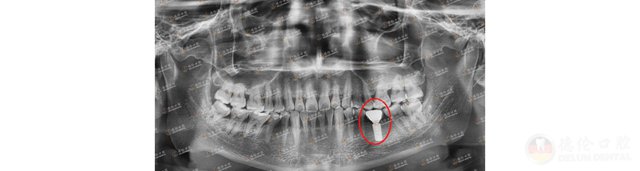

德伦口腔东风总院口腔种植科副主任罗朝阳拔除掉刘叔无保留意义的松动牙后,为刘叔进行即拔即种、即刻负重手术。即拔即种、即刻负重的优势之一是能缩短治疗周期,减少手术和诊疗次数。

罗主任为刘叔进行即拔即种、即刻负重手术,刘叔得以重获一口好牙

罗主任在刘叔上下颌各植入6颗种植体,术后当天取模,一周左右在植体上部搭配连桥冠恢复全口牙的生理功能。

种牙治疗结束后,刘叔的好牙又回来了。为感谢罗主任,刘叔将三面锦旗赠与罗主任团队,向罗主任团队表达浓浓的谢意。